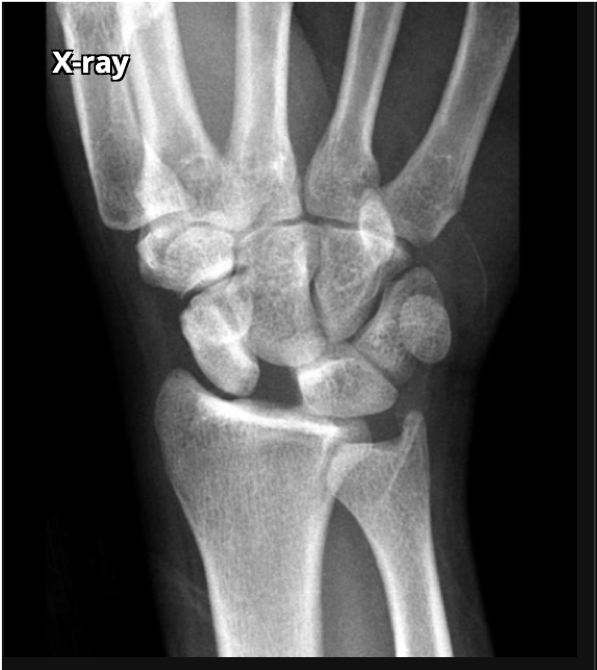

Normal or abnormal alignment?

Normal alignment